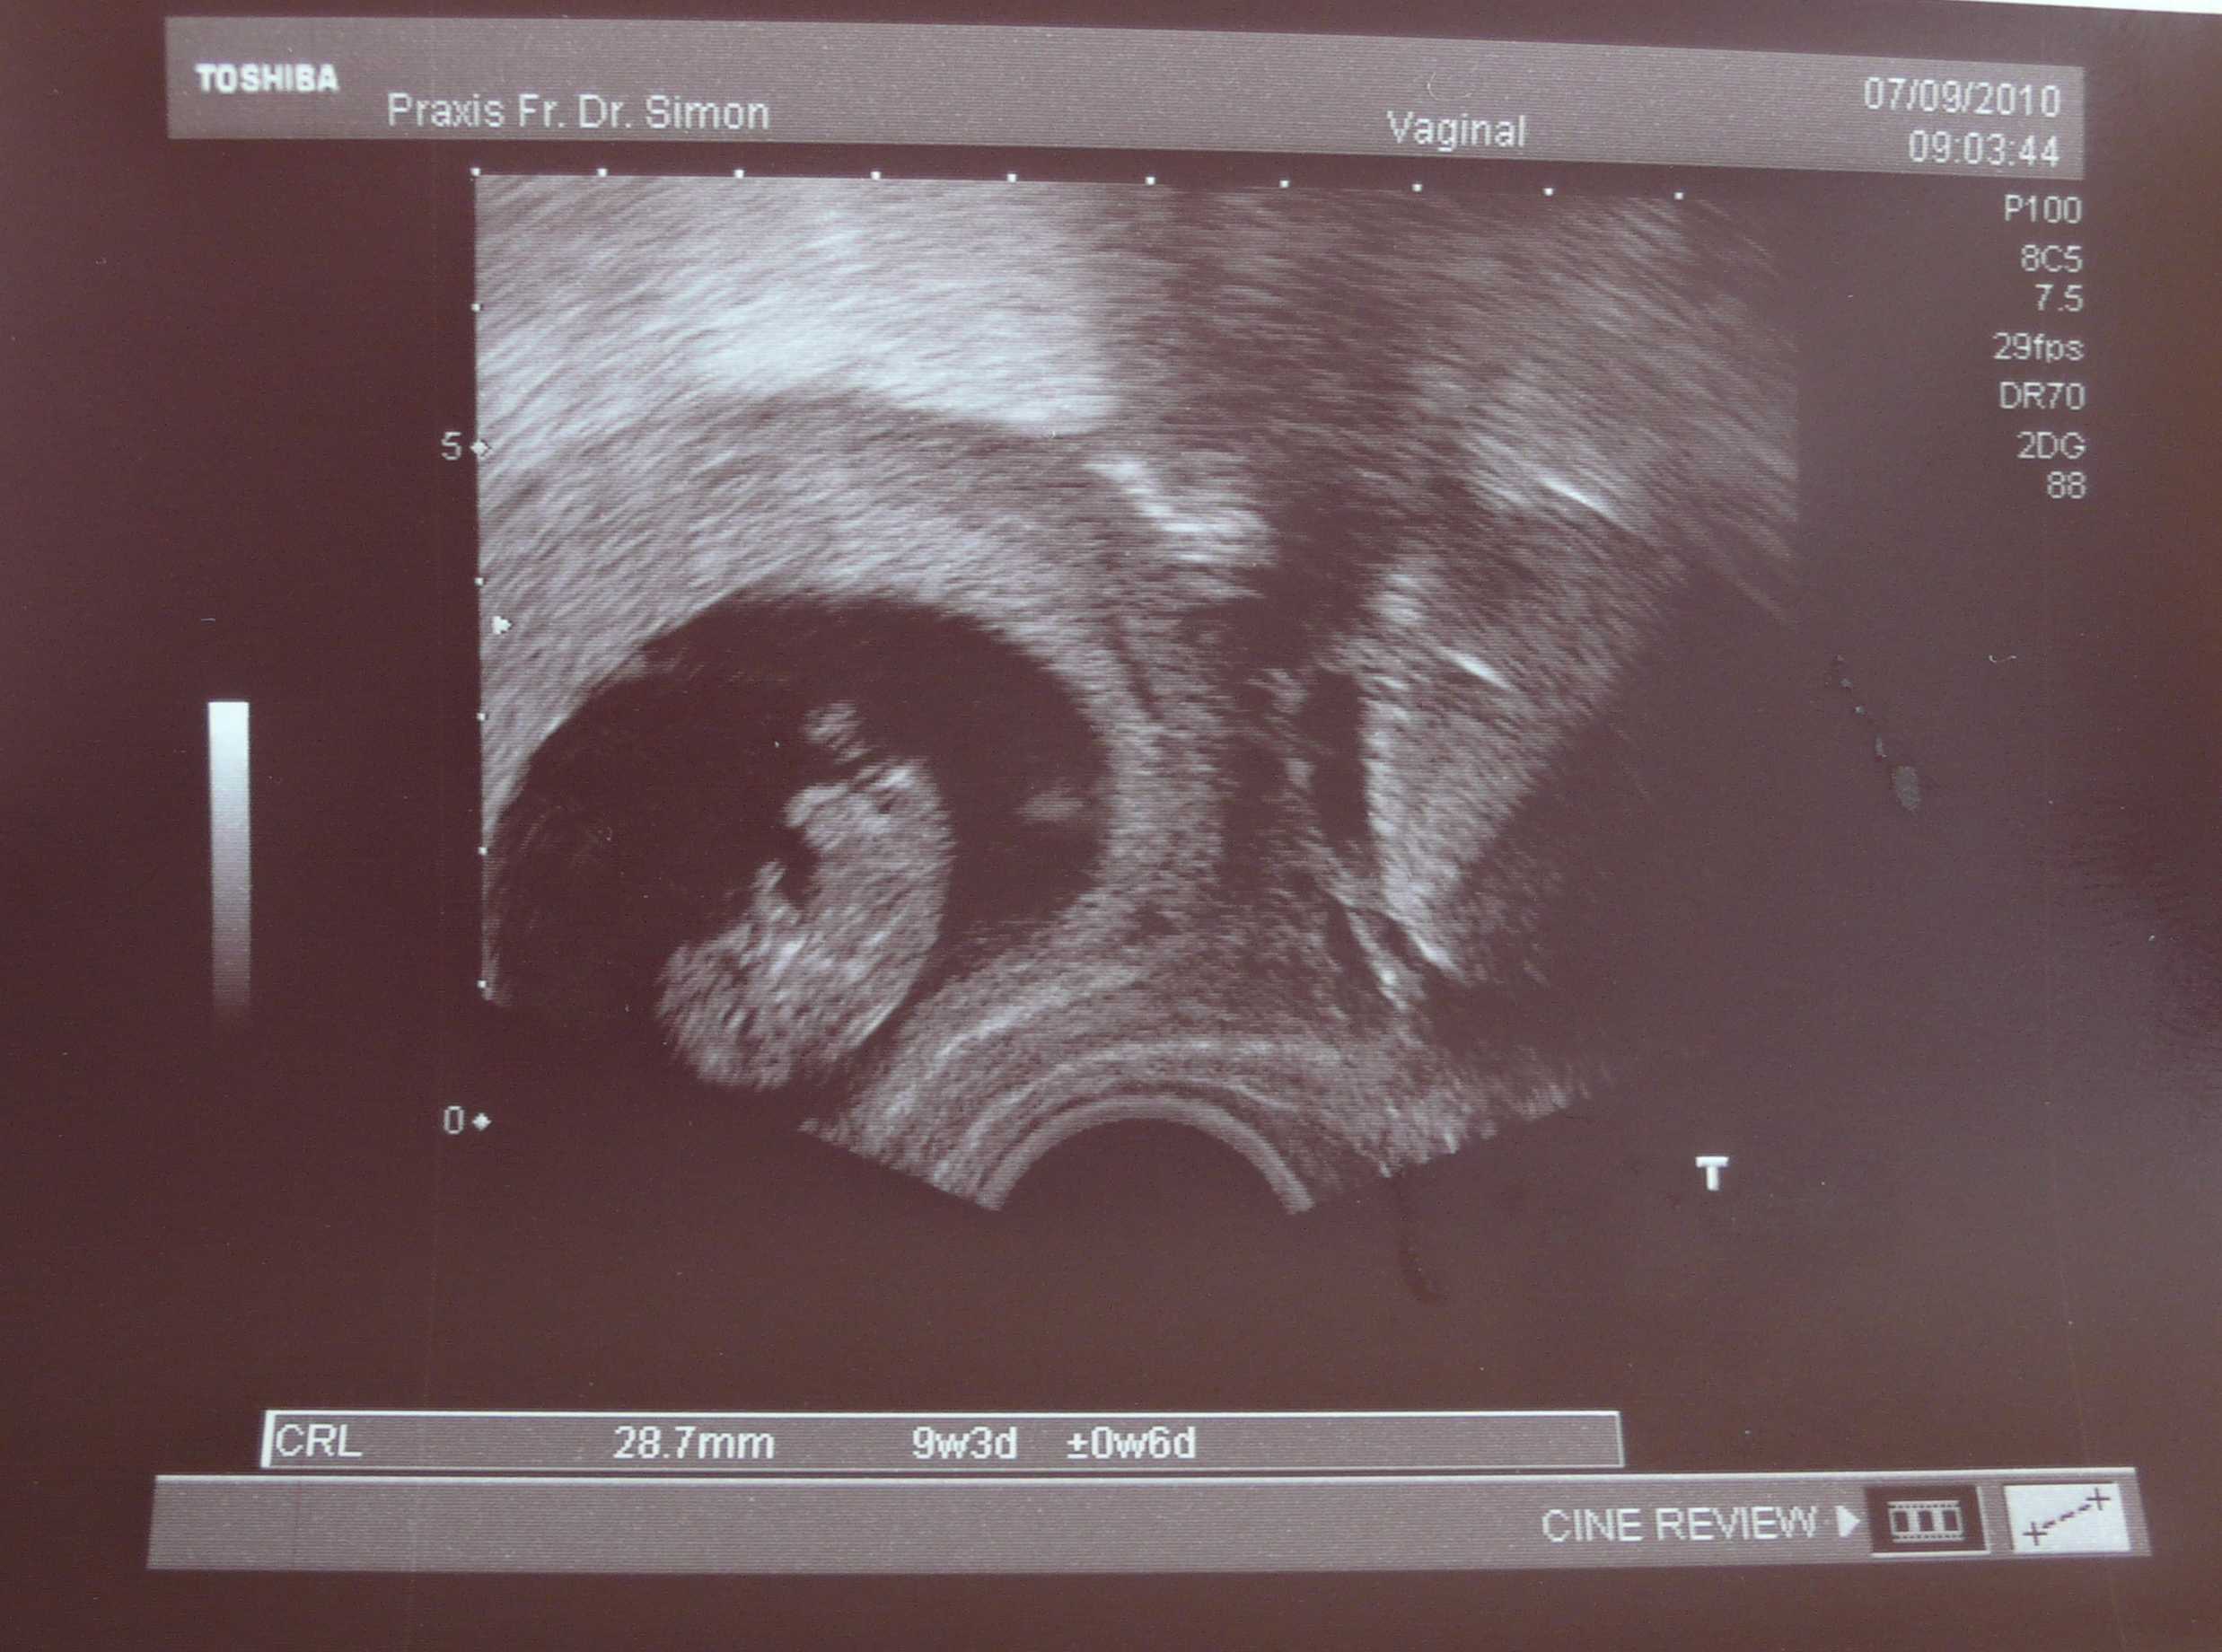

@Liebe Maiar-Steffi: WOW, das ist ein echt superschönes Bildchen

Voll niedlich und man kann alles so super erkennen!!! Wahnsinn, wie super ein US-Gerät funktionieren kann. Herzlichen Glückwunsch zum MuPa